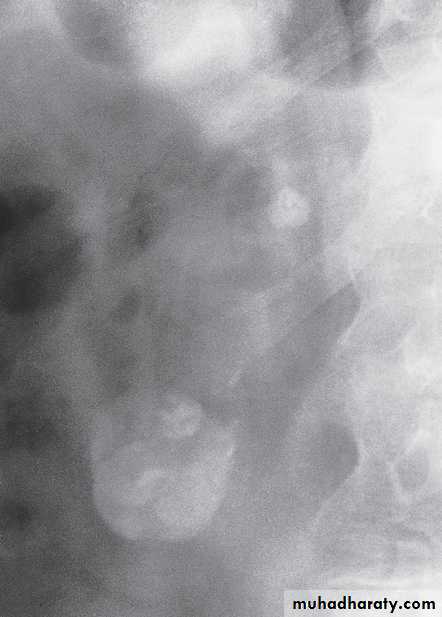

• Calcification is common. Usually, there are one o more foci of irregular calcification, but in advanced cases with longstanding tuberculous pyonephrosis the majority of the kidney and hydronephrotic collecting system may be calcified, leading to a so-called autonephrectomy. Calcification implies healing but does not mean that the disease is inactive.

• The earliest change on the post contrast films is irregularity of a calix. Later, a definite contrast-filled cavity maybe seen adjacent to the calyx.

• Strictures of any portion of the pelvicaliceal system or ureter may occur, producing dilatation of one or more calices.

The multiplicity of strictures is an important diagnostic feature.